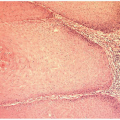

![]() Figure 7.8. Granular cell tumor in the right labium majus. This had been removed 9 years before and had recurred recently in the same location. |